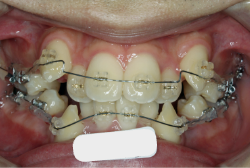

本症例では、逆転している前歯の重なりを出来るだけ短期間で解消する必要があります。そこでまず下の前歯を内側へ入れる準備を進め、その後、上の前歯を外へ出すのと同時に下の歯を内側に入れる治療をします。この治療段階では上下前歯が非常に強く当たらざるを得ない時期があり、このような衝撃の強い噛み合わせは(咬合性外傷と言います)、歯の破折、歯根吸収、歯肉退縮などを引き起こす可能性があります。そこで、この期間を最短で済ませるために上下で開始時期をずらしたりいろいろな工夫が必要となります。

初診時の状態ですが、前歯の噛み合わせが逆転していて、下の前歯が外側に来て、上の前歯が裏側になっています。口元の様子ですが、前歯の重なり方が逆なので、唇の様子もそれを反映して、下唇が突出しています。反対咬合としてはかなり重症です。

分析してみると歯の傾き方に問題があるだけでなく、顎の骨の大きさと形にも問題があることが分かりました。ただし、骨の問題点が見つかったからと言って、必ずしも外科矯正になるわけではなく、このくらいの症状ですと、通常の矯正でもきれいに治すことができます。

診断の結果、下の前歯を正しい位置まで内側に入れていくためには、十分な隙間を確保することが避けられないと判断し、上の左右第二小臼歯と下の左右第一小臼歯は抜歯させて頂くことにしました。歯の本数は減りましたが、歯科医学的評価も大きく改善しましたし、審美的にも大幅な改善が見られますね。特に口元の様子が全然変わりました。